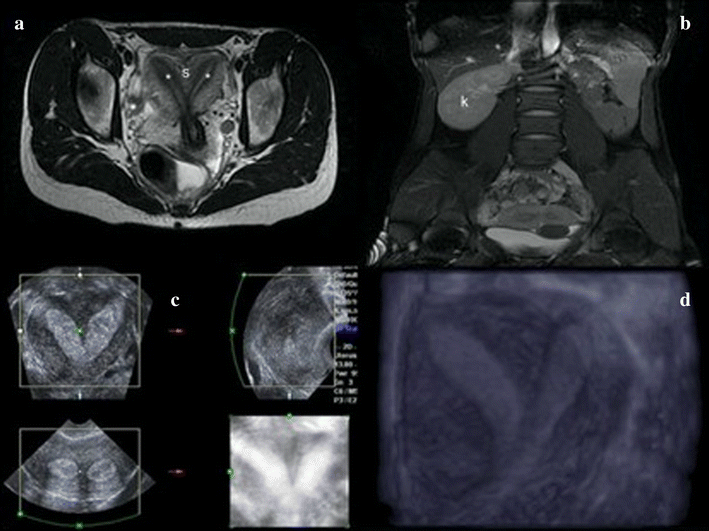

Septate Uterus Ultrasound Diagnosis Symptoms and Treatment [Updated Septic Uterus Treatments Dilation and curettage (d&c) is a surgical procedure that opens the cervix and uses a thin instrument to remove tissue from the inside of the uterus. The condition can be treated with surgery which has shown to significantly improve outcomes. It is often done after a miscarriage, and is. It’s possible for a septate uterus to be misdiagnosed as a. Septic Uterus Treatments.

Figure 1 from Septum resection for women of reproductive age with a Septic Uterus Treatments Dilation and curettage (d&c) is a surgical procedure that opens the cervix and uses a thin instrument to remove tissue from the inside of the uterus. The condition can be treated with surgery which has shown to significantly improve outcomes. It is often done after a miscarriage, and is. El tratamiento del septo uterino y los resultados asociados con la. Septic Uterus Treatments.

Oblique Cervical Septum with Complete Uterine Septum Diagnosis and Septic Uterus Treatments It is often done after a miscarriage, and is. In patients with a symptomatic septate uterus hysteroscopic septoplasty is a safe and effective procedure. Septate uterus is when a membrane, the septum, forms in the uterus and divides the inner portion of the uterus. Surgery was traditionally done by a transabdominal approach but recently a hysteroscopic approach has been proposed,. Septic Uterus Treatments.